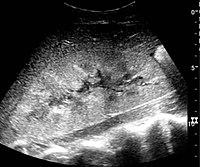

In medical imaging, the acute changes in the kidney are often examined with renal ultrasonography as the first-line modality, where CT scan and magnetic resonance imaging (MRI) are used for the follow-up examinations and when US fails to demonstrate abnormalities. In evaluation of the acute changes in the kidney, the echogenicity of the renal structures, the delineation of the kidney, the renal vascularity, kidney size and focal abnormalities are observed.[16] CT is preferred in renal traumas, but US is used for follow-up, especially in the patients suspected for the formation of urinomas. A CT scan of the abdomen will also demonstrate bladder distension or hydronephrosis. However, in AKI, the use of IV contrast is contraindicated as the contrast agent used is nephrotoxic.

16. ^ a b c d Content initially copied from: Hansen, Kristoffer; Nielsen, Michael; Ewertsen, Caroline (2015). "Ultrasonography of the Kidney: A Pictorial Review". Diagnostics. 6 (1): 2. doi:10.3390/diagnostics6010002. ISSN 2075-4418. PMC 4808817. PMID 26838799. (CC-BY 4.0) Archived 2017-10-16 at the Wayback Machine